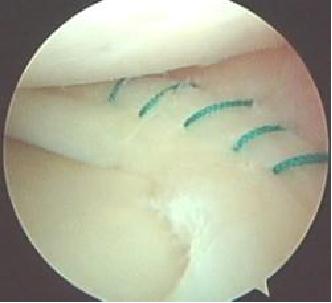

2、半月板损伤:

半月板损伤

半月板是我们膝关节内起稳定和缓冲作用的保护装置,一旦半月板损伤,我们会出现关节绞索、打软退及关节疼痛等症状。X线和CT不能看到半月板,所以我们必须借助核磁共振。但是,在核磁共振上,毕竟是间接去看,我们可能会出现漏诊、误诊等情况,有时候还会因为伪影而被干扰。

所以关节镜就是一个非常不错的检查,它能够直接看到半月板的损伤,并且,如果条件符合,可以给与积极治疗,上图就是半月板缝合后的镜下情况。

具体半月板缝合的条件,我后面再具体和大家解释。